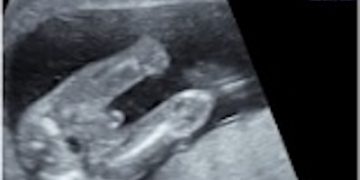

Leggi di piùCari colleghi, vi presentiamo la guida al counseling di Gennaio 2025 su oloprosoencefalia!! Potrete scaricarla cliccando sul link. Grazie a Daniele Di Mascio! ...